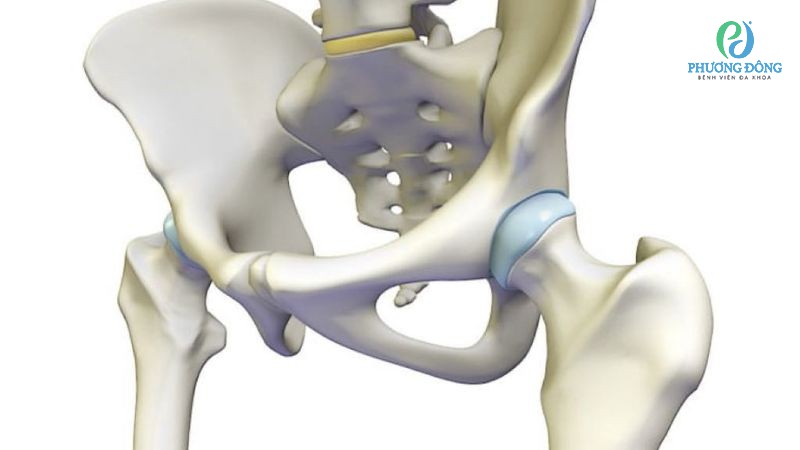

Khớp háng

Khớp háng có bao hoạt dịch lớn nhất nằm ở mấu chuyển lớn, giữa cơ mông và mấu chuyển. Với vị trí này, bao khớp hỗ trợ giảm ma sát khi cơ thể chạy nhảy, xoay hông hoặc đi bộ, đảm bảo khả năng vận động linh hoạt và dễ dàng.

Bao khớp háng lớn nhất nằm ở giữa cơ mông và mấu chuyển